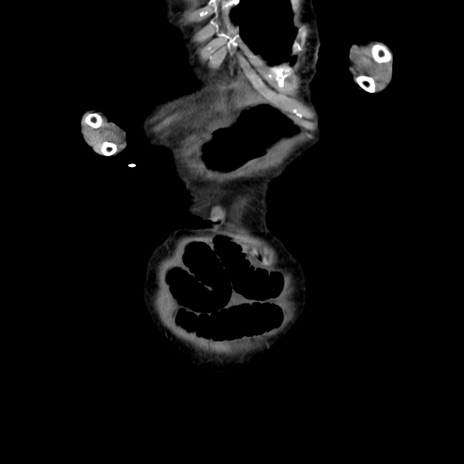

症例27(冠状断像)

横断像